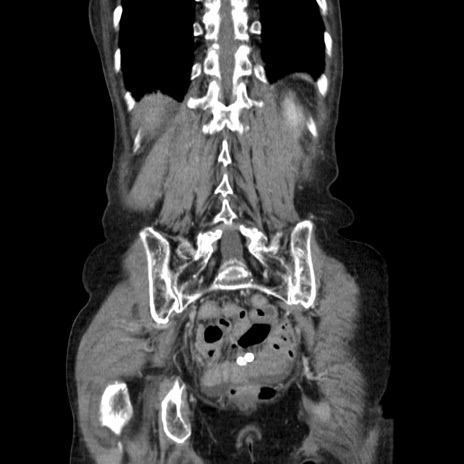

症例25(冠状断像)

【症例】80歳代女性

【主訴】胸のつかえ感

【現病歴】約9時間前に食後から胸のつかえた感じあり、嘔吐あり、来院。

【既往歴】胃癌(全摘)、胆摘、虫垂炎

【身体所見】心窩部に圧痛あり、反跳痛なし。

【データ】WBC 5700、CRP 0.05